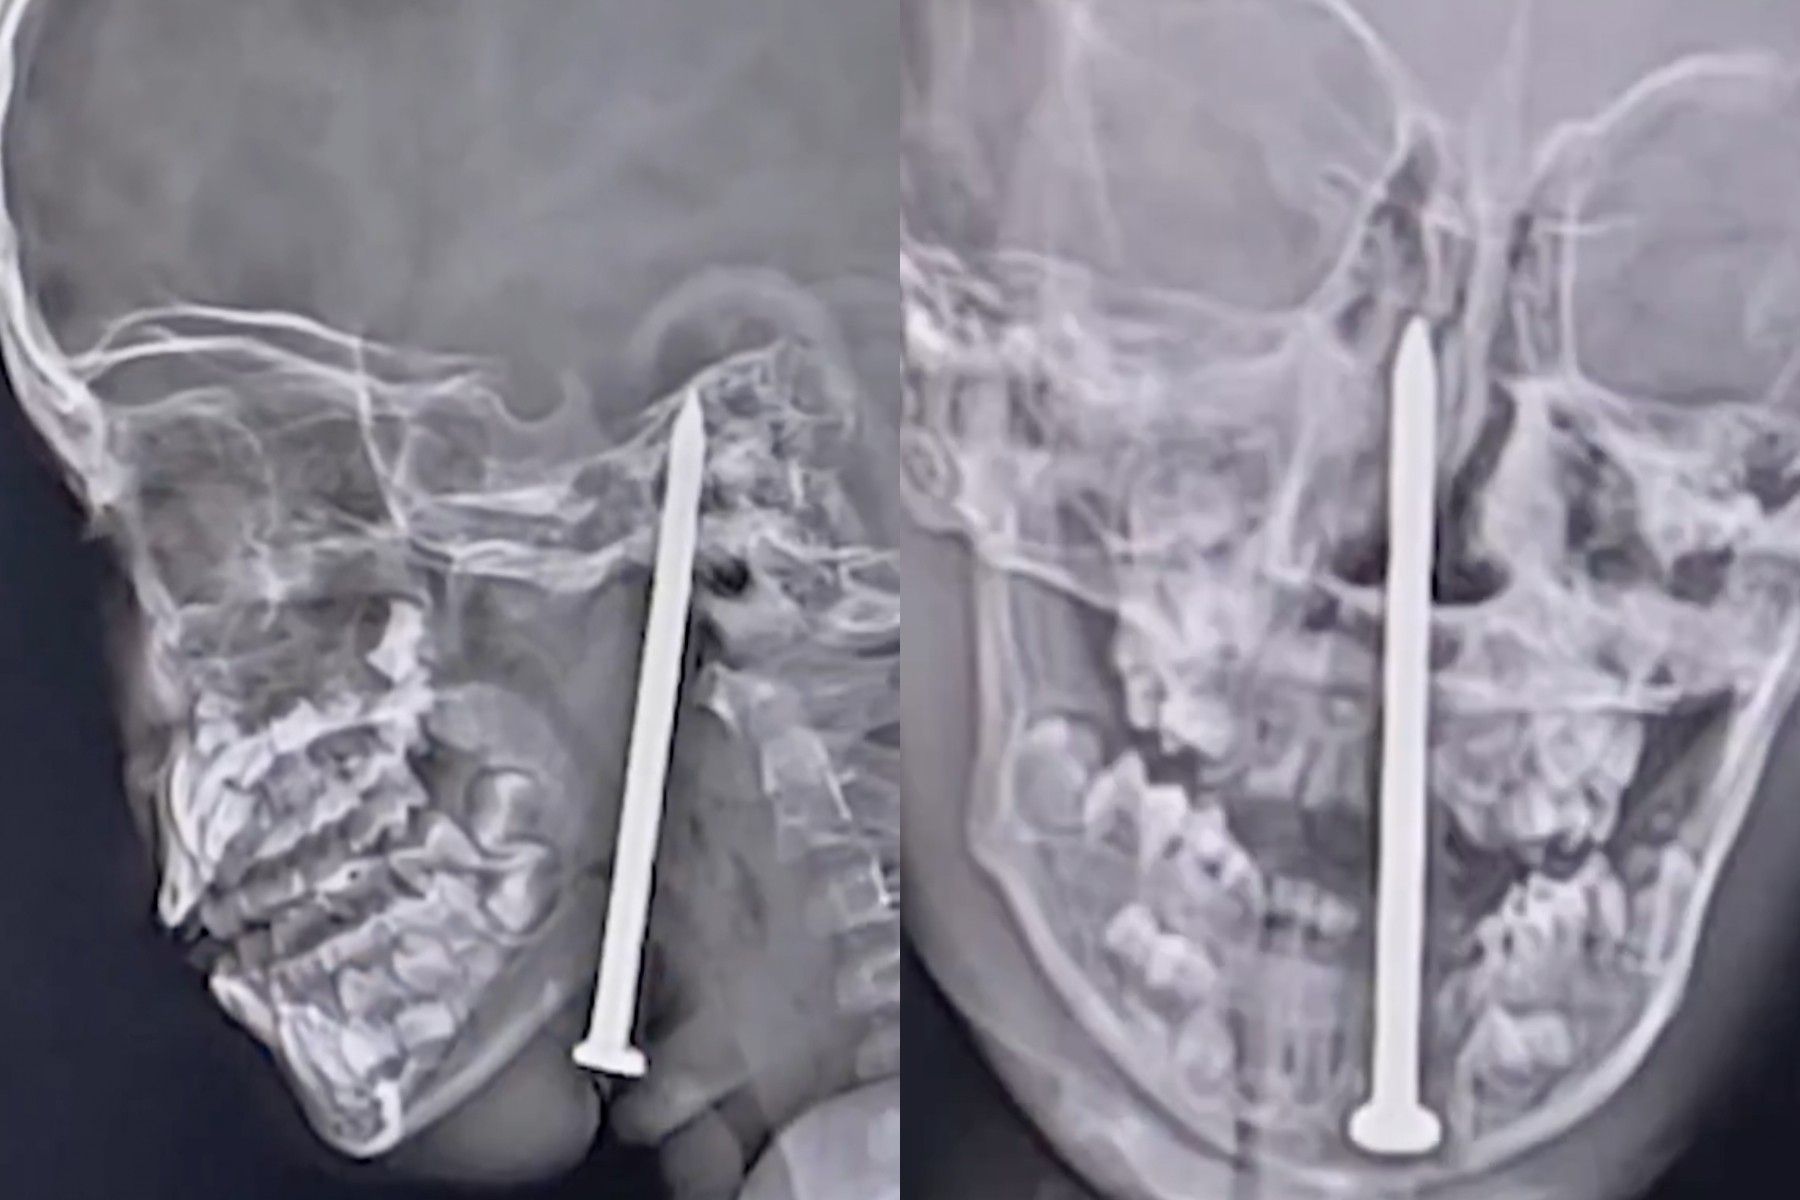

Menino de 7 anos sobrevive a prego no cérebro na Índia

Menino de 7 anos sobrevive a acidente com prego no pescoço, passando por cirurgia complexa.; Reprodução: Globo

Na Índia, um menino de apenas 7 anos passou por um incidente extraordinário ao ter um prego de 7,5 centímetros perfurando seu cérebro. O acidente ocorreu no distrito de Balrampur, onde a criança caiu sobre o objeto enquanto brincava. Apesar da gravidade, o pequeno sobreviveu sem danos em vasos vitais.

O menino foi rapidamente transportado para o King George's Medical University (KGMU), em Lucknow, após a queda, onde os médicos realizaram uma cirurgia complexa para remover o prego. O procedimento, que durou cerca de quatro horas, foi bem-sucedido, e ele agora está se recuperando na Unidade de Terapia Intensiva (UTI) pediátrica.

Imagens de ressonância magnética mostraram a trajetória do prego, que foi inserido desde a parte inferior da mandíbula até o interior do crânio. Médicos enfatizaram que, caso o prego tivesse atingido um vaso sanguíneo ou uma área crítica do cérebro, o resultado poderia ter sido fatal. O cirurgião Sandip Tiwari relatou que o prego havia migrado para o cérebro sem causar danos significativos.

A operação foi realizada pela equipe médica, incluindo Samir Misra, membro da equipe de trauma. Ele destacou a necessidade de precisão durante a cirurgia devido aos enormes riscos envolvidos. "Qualquer erro poderia ter consequências fatais", afirmou Misra.

Após a cirurgia, o superintendente médico do hospital anunciou que o caso será documentado e relatado em uma revista científica internacional, contribuindo com a medicina e oferecendo conhecimento valioso para a comunidade médica global.

Este caso é uma demonstração impressionante da resiliência humana e dos avanços médicos que podem garantir a vida em situações extremas. O menino continua em recuperação, e os profissionais de saúde permanecem otimistas quanto ao seu processo de cura.